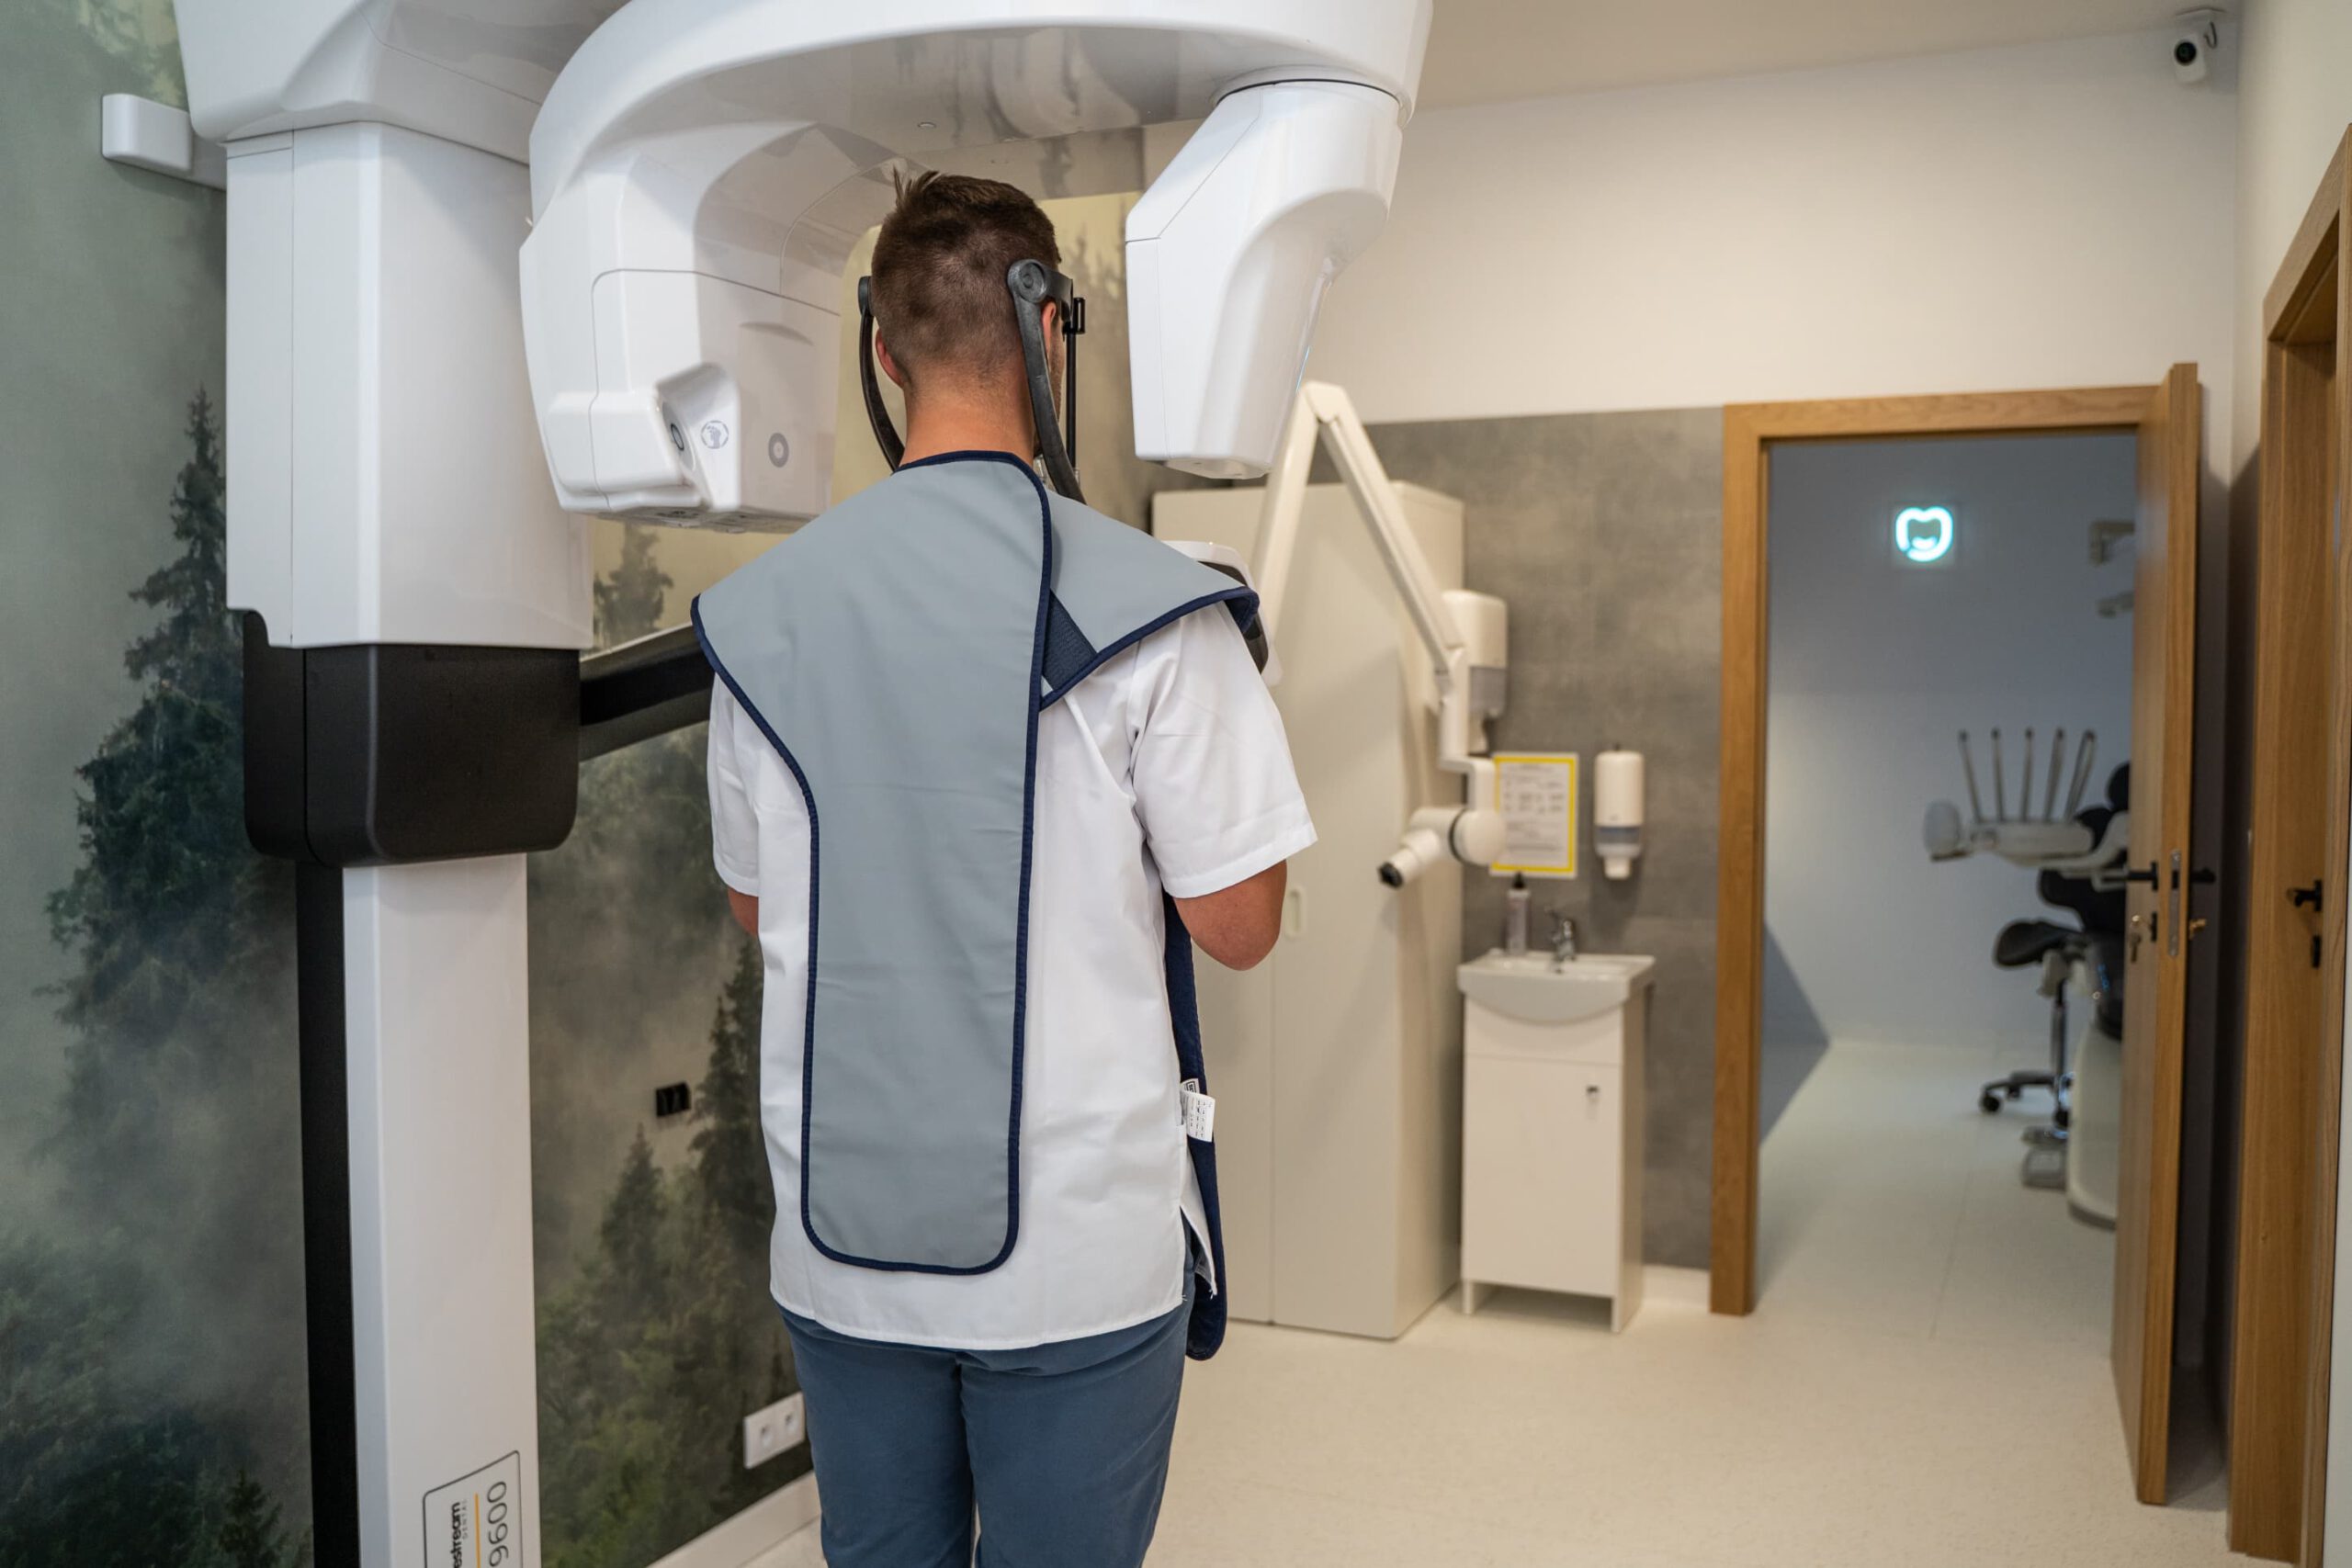

Tomograf Kodak Carestream CS 9600 jest to system, który zapewnia najwyższą dostępną jakość uzyskiwanych obrazów oraz aż czternaście różnych pól obrazowania. Zastosowane w nim innowacyjne rozwiązania pozwoliły na osiągnięcie doskonałych efektów, przy jednoczesny zwiększeniu bezpieczeństwa użytkowania. Dzięki licznym funkcjom sprawdza się jako urządzenie diagnostyczne w wielu dziedzinach stomatologii. Tomografia wykonana przy jego użyciu jest przy tym wyjątkowo dokładna. Oznacza to, że podczas badania można bardzo precyzyjnie zobrazować wszystkie tkanki organizmu – to pozwala na szybkie postawienie jednoznacznej diagnozy oraz natychmiastowe wdrożenie odpowiednich metod leczenia.

Tomograf Kodak Carestream CS 9600 jest to system, który zapewnia najwyższą dostępną jakość uzyskiwanych obrazów oraz aż czternaście różnych pól obrazowania. Zastosowane w nim innowacyjne rozwiązania pozwoliły na osiągnięcie doskonałych efektów, przy jednoczesny zwiększeniu bezpieczeństwa użytkowania. Dzięki licznym funkcjom sprawdza się jako urządzenie diagnostyczne w wielu dziedzinach stomatologii. Tomografia wykonana przy jego użyciu jest przy tym wyjątkowo dokładna. Oznacza to, że podczas badania można bardzo precyzyjnie zobrazować wszystkie tkanki organizmu – to pozwala na szybkie postawienie jednoznacznej diagnozy oraz natychmiastowe wdrożenie odpowiednich metod leczenia.

W zależności od rozmiaru zdjęcia, tomograf Kodak Carestream CS 9600 emituje od 5 do 14-19 μSv promieniowania rentgenowskiego, co jest dawką nawet o 85% niższą niż w przypadku innych sprzętów. Co istotne, tomograf Kodak Carestream CS 9600 jest idealny do badań typowych dla każdej specjalizacji stomatologicznej oraz laryngologicznej (badanie zatok przynosowych lub skalistości kości skroniowych). Sprawdzi się w przypadku pacjentów implantologicznych, ortodontycznych, periodontologicznych, endodontycznych czy chirurgicznych.